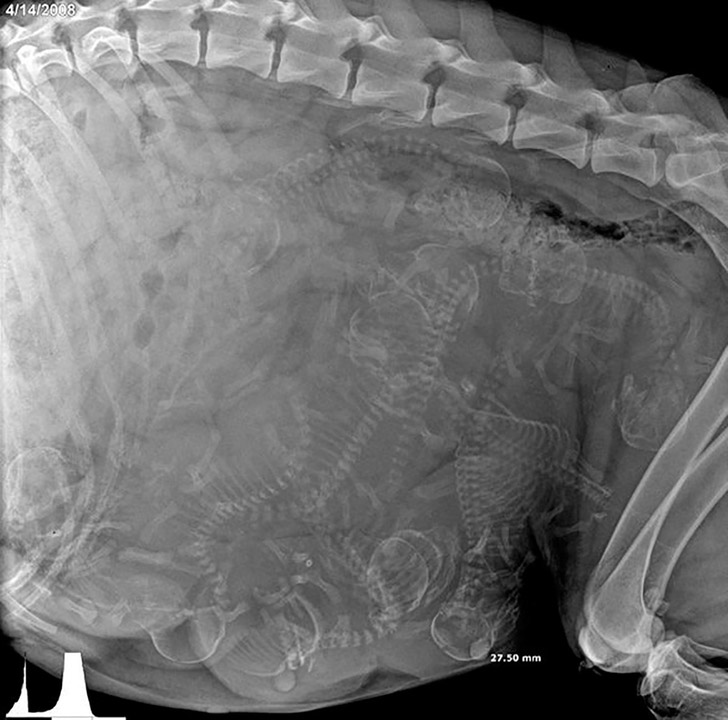

1. Рентген беременной собаки